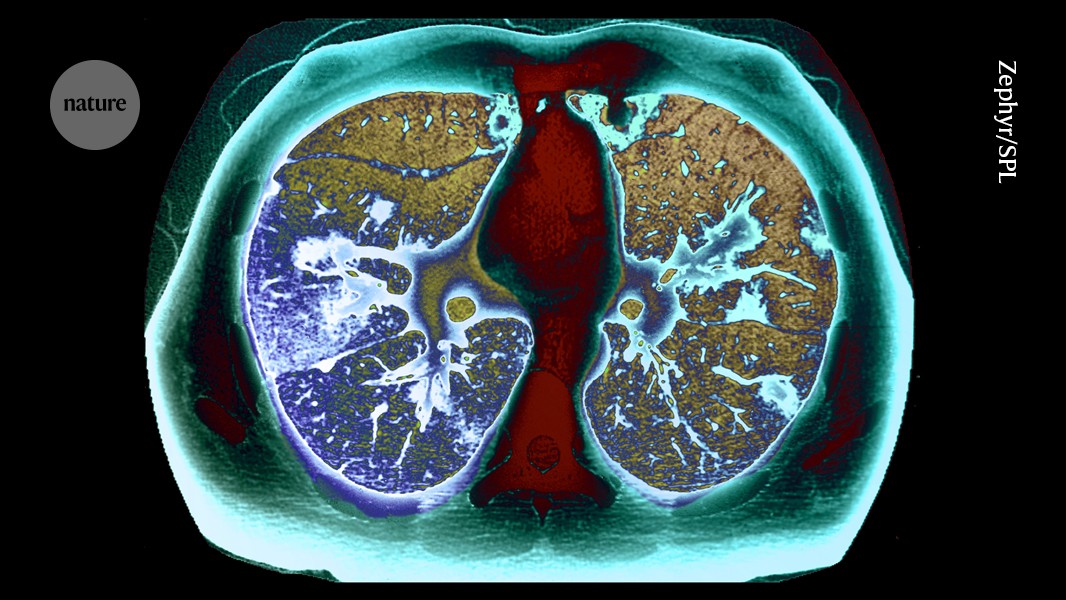

Huge lung-cancer screening campaign boosts early diagnosis